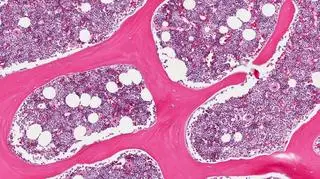

Naukowcy z Uniwersytetu Harvarda mają coraz większe szanse na stworzenie leku na raka. Eksperci wyprodukowali komórki macierzyste, które potrafią wydzielać substancje toksyczne dla komórek nowotworowych, nie niszcząc przy tym zdrowych komórek. Mimo że jest jeszcze zbyt wcześnie, by mówić o przełomie, to badania dają wielkie nadzieje na przełom w leczeniu kolejnych zachorowań.

Zespół inżynierów genetycznych stworzył komórki macierzyste, które produkują toksyny (tzw. PE) szkodliwe dla guzów mózgu. Toksyny te zwalczają komórki nowotworowe, ale nie wpływają na zdrowe komórki organizmu.

W jaki sposób naukowcom udało się dostarczyć toksyczne związki do nowotworów tak, by nie zaszkodziły innym komórkom? Podczas testów komórki macierzyste zostały zaaplikowane w żelowe otoczki. Później zostały one umieszczone w miejscu po usuniętym guzie.